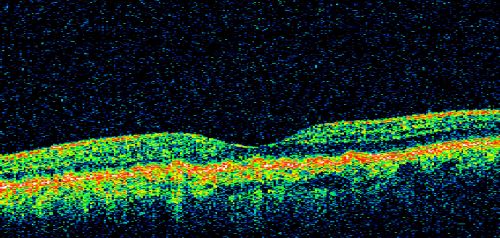

Basal Laminar (cuticular) Drusen both eyes 60 Year Old Woman

60-year-old woman with minimal vision loss. Vision OD is 20/30 OS 20/40